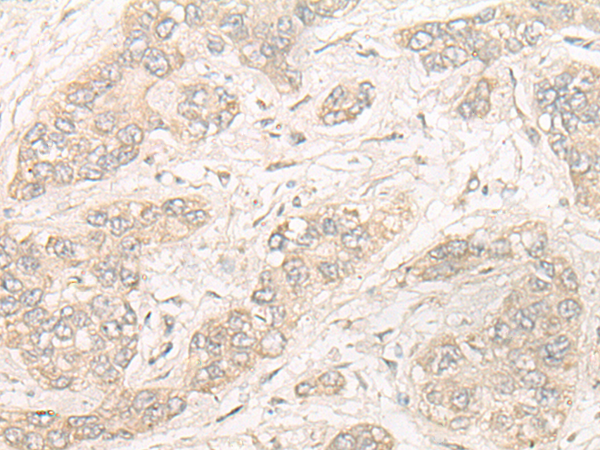

分类: 科研抗体货号: P09632别名: VIB1B; PtdInsTP; PI-TP-beta应用: WB,IHC反应种属: Human, Mouse, Rat